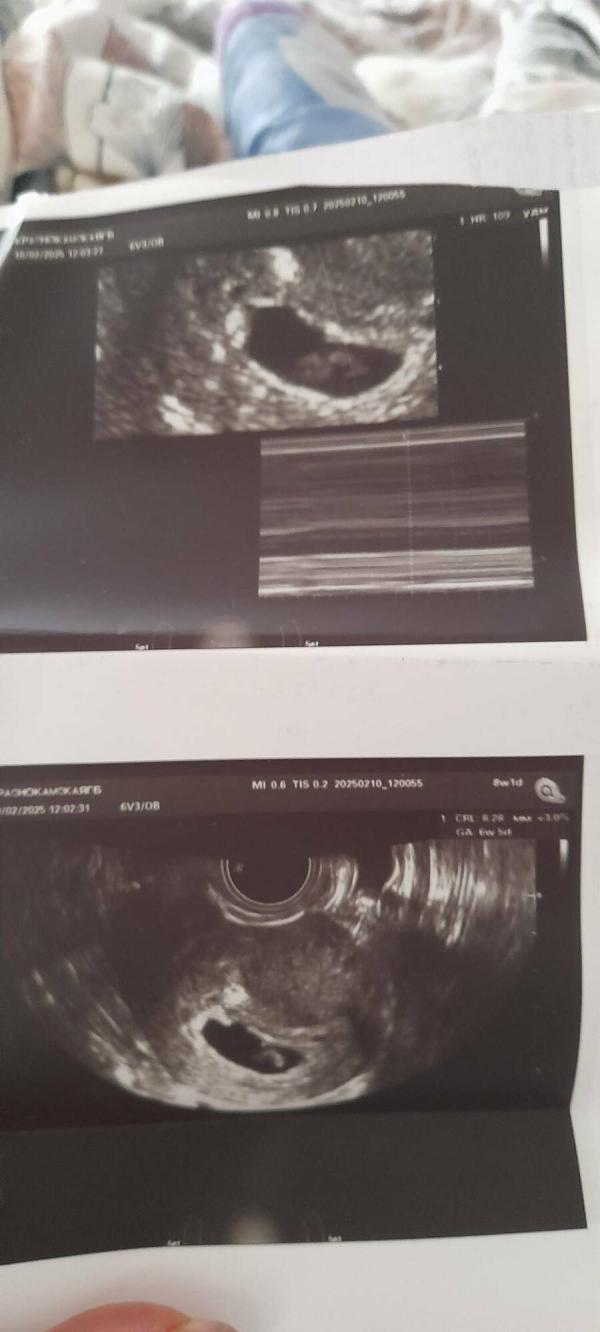

УЗИ на 6,5 неделях: сердечко бьется, все хорошо! Делюсь радостью и сроком беременности

Сходила повторно на узи. Лялечка появилась, сердечко бьется, все отлично, я счастлива🥰срок поставили 6,5 недель